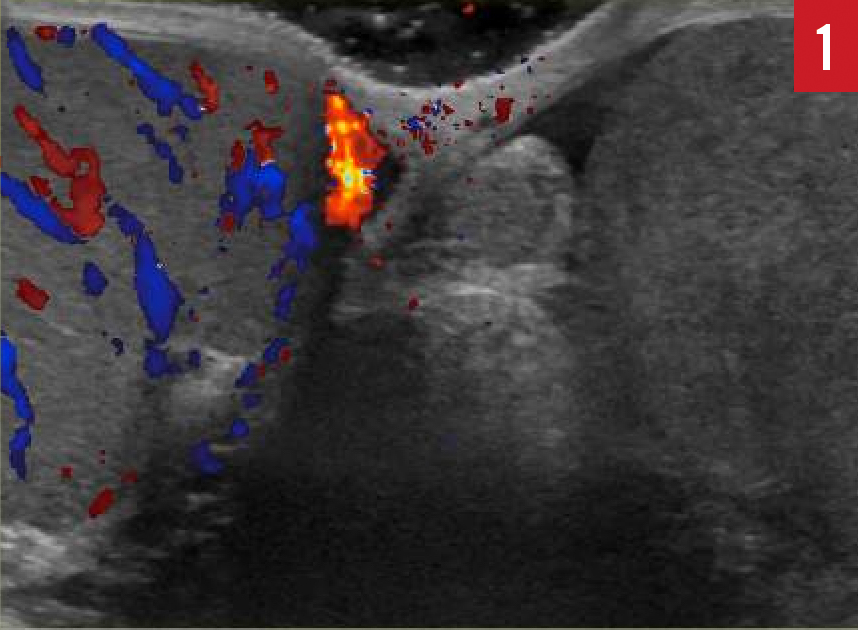

Shraddha Mittal, MD

A 16-year-old healthy boy with no significant past medical history presented to the emergency department (ED) with sudden-onset, severe, sharp, intermittent lower abdominal pain, worse on the left side,...